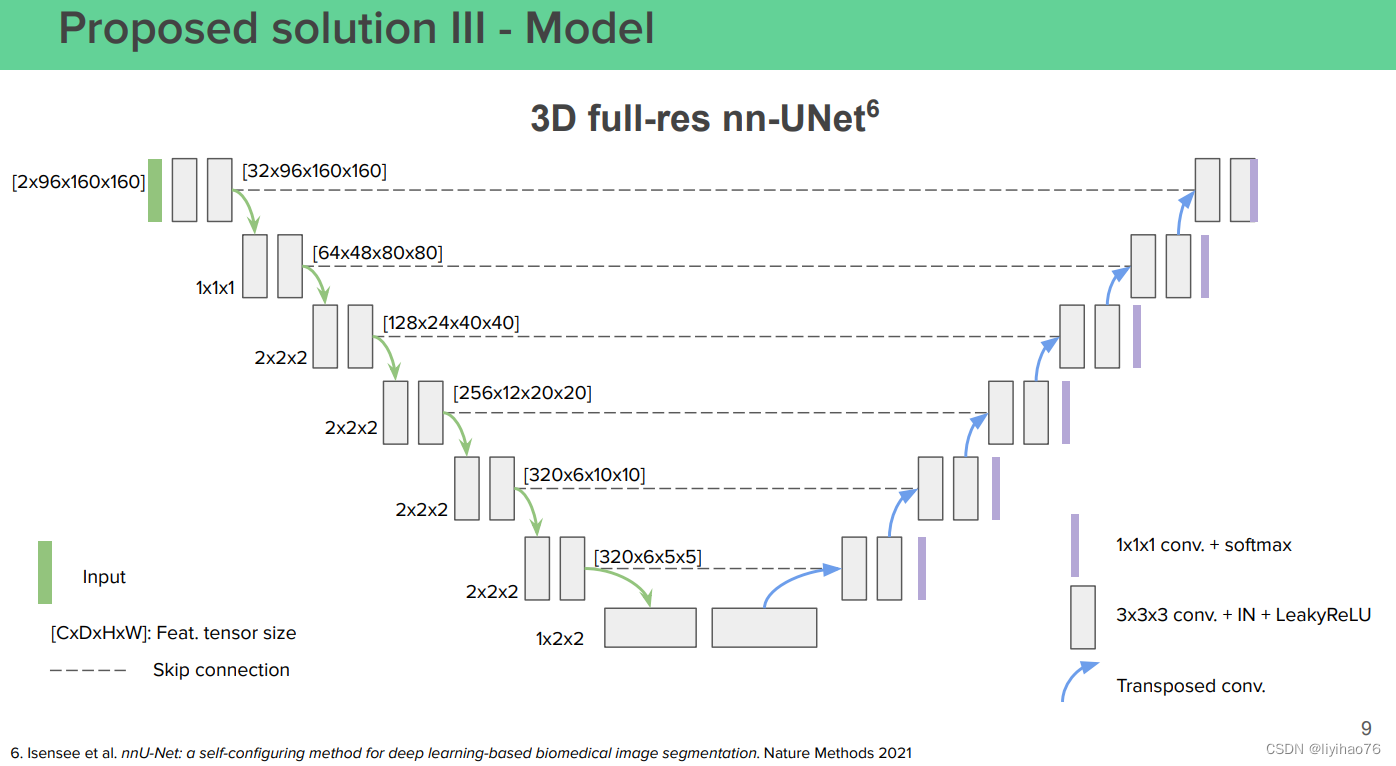

(0) 方法:Extending nnU-Net

- Isensee 等人的 nnU-Net。 是 BraTS 2020 的获奖作品。由于 nnU-Net 易于适应新数据集以及完全开源的代码和模型,nnU-Net 可以作为进一步实验的极好基线。

- 考虑到 APIS 数据集包含许多小目标样本,我们通过以下修改扩展 nnU-Net:

- 我们将patch size 从原来的 [24, 192, 160] 更改为 [16, 128, 128]。

- nnU-Net 的验证损失默认使用batch dice loss,我们将其更改为instance dice loss。

- 对于NCCT 分割任务,我们仅使用 CT 图像来训练 nnU-Net。 nnU-Net 的“ct”方案用于预处理。 我们将默认的补丁大小更改为 [16, 128, 128]。 其他超参数保持不变。

- 对于 ADC 分割任务,我们仅使用 ADC 图像来训练 nnU-Net。 nnU-Net 的“non-ct”方案用于预处理。 我们将默认的补丁大小更改为 [16, 128, 128]。 其他超参数保持不变。

- nnU-Net 在3D分割任务中依旧表现优异,数据预处理的不同可能会对分割表现有较大影响。